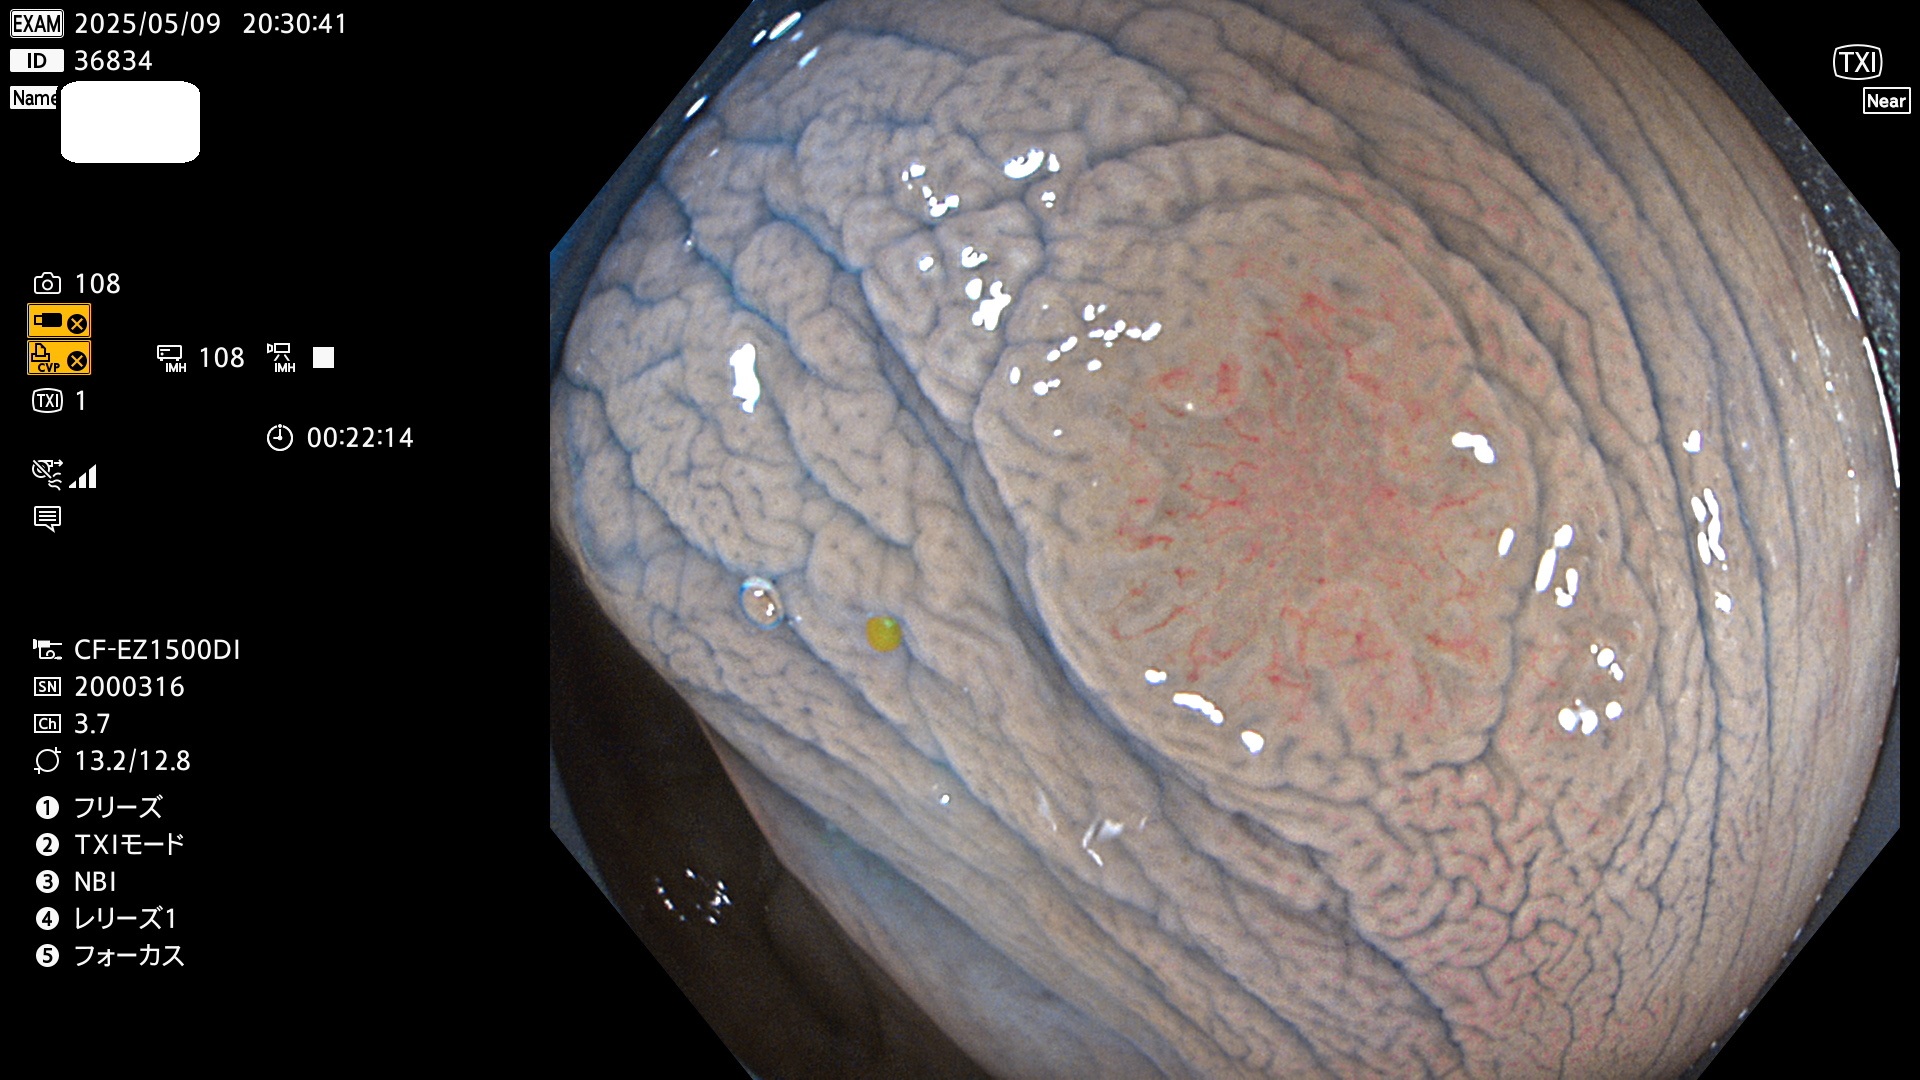

完全に平坦な物をUb、陥凹している物をUcと呼びます。Ubは認識が困難で、Ucはびらん(炎症)と紛らわしいために見落とされやすく、「内視鏡後・大腸癌」の原因になります。

抽出の対象期間 2025年5月8日〜5月11日の4日間(48件の検査)14個 (14/48=29%)